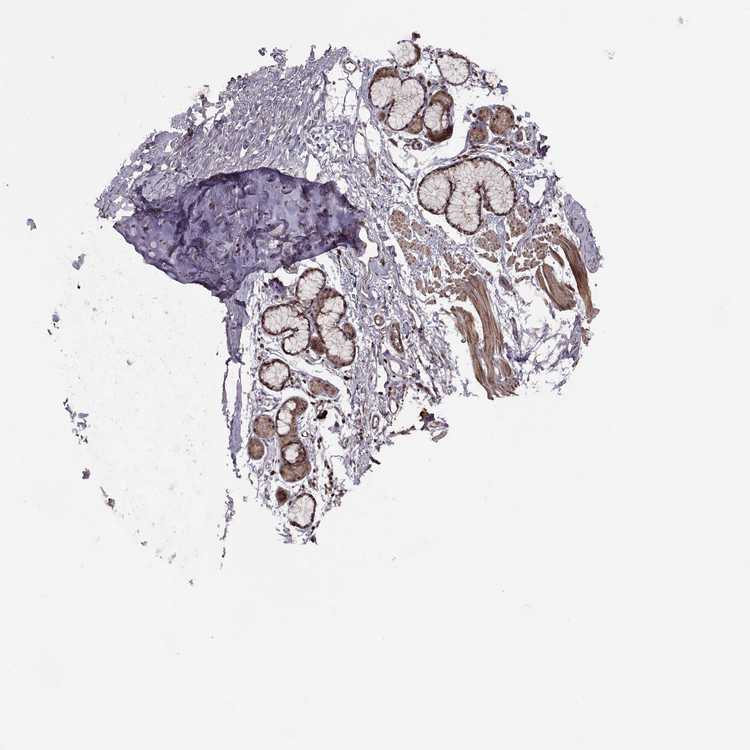

SOFT TISSUE 1 - Antibody stainingi

Antibody staining in the annotated cell types in the current human tissue is reported as not detected, low, medium, or high, based on conventional immunohistochemistry profiling in selected tissues. This score is based on the combination of the staining intensity and fraction of stained cells.

Each image is clickable and will lead to virtual microscopy that enables deeper exploration of all samples and also displays staining intensity scores, fraction scores and subcellular localization as well as patient and tissue information for each sample.

Antibody HPA075125

Chondrocytes Medium

Fibroblasts Medium